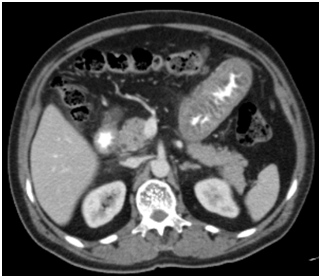

A 57year-old male presented to the Emergency Department (ED) with abdominal pain and nausea for 12hours. He had been hospitalized several times for abdominal pain in many different centers. In the ED, he was found to have moderate tenderness in all quadrants with a mild leukocytosis. His amylase level was 342U/L (normal: 23-85U/L) and lypase level was 550U/L (normal: 0-160U/L). He was admitted to the gastroenterology clinic with an initial diagnosis of pancreatitis and started on intravenous hydration. Ultrasonography revealed a normal-appearing pancreas and free fluid in Morison’s pouch and his right lower quadrant. In the left upper and lower quadrants, the bowel wall appeared diffusely thickened and echogenic with a narrowed, hypoechoic lumen. A diagnostic paracenthesis was performed and his serum ascites albumin gradient (SAAG) was found to be lower than 1.1. Peritoneal fluid cytologic examination revealed reactive mesotelial cells and no sign of malignancy. CT scan of the abdomen following intravenous and oral administration of contrast medium revealed a regular wall thickening of the duodenum and proximal jejunum with thickened mucosal folds (Figure 1). A CT Angiography was performed with the initial diagnosis of bowel ischemia. However, mesenteric vessels were totally normal. Five days after his admission, his abdominal pain completely relieved and Ultrasonograpy showed that his intestinal walls had returned to normal and ascites had disappeared. He was discharged but referred again with same complaints four days later. He was found to have tenderness in all quadrants with a mild leukocytosis and the bowel wall appeared diffusely thickened on Ultrasonography just like his previous admission. An upper gastrointestinal endoscopy was performed. Duodenal and jejunal wall biopsies revealed mild inflammation. His colonoscopy was totally normal. He was discharged after his symptoms improved. On his third hospitalisation with same reason on our center, a diagnostic laparotomy was performed and no gross pathology other than edematous omentum was observed. Omental biopsy revealed congestion, mature adipose tissue with minimal inflammation. To exclude the diagnosis of Familial Mediterranean Fever (FMF) which is common in Turkey and is a cause of recurrent peritonitis, FMF mutation panel with common mutations was requested and found to be normal. He was discharged after his abdominal pain gradually decreased and his laboratory results normalized. 5days after discharge, he presented with the same clinical picture and he was suspected of having hereditary angioedema and a reduced C1-INH protein level of 4mg/dL (Normal: 11-26mg/dL) was detected together with markedly lower C1-INH activity of <10% (Normal: 70-130%) and he was diagnosed with hereditary angioedema. He started on danazol. After Danazol treatment, he only had a mild episode over 3years of follow-up.

Figure 1 Regular wall thickening of the duodenum and proximal jejunum with thickened mucosal folds on CT scan.